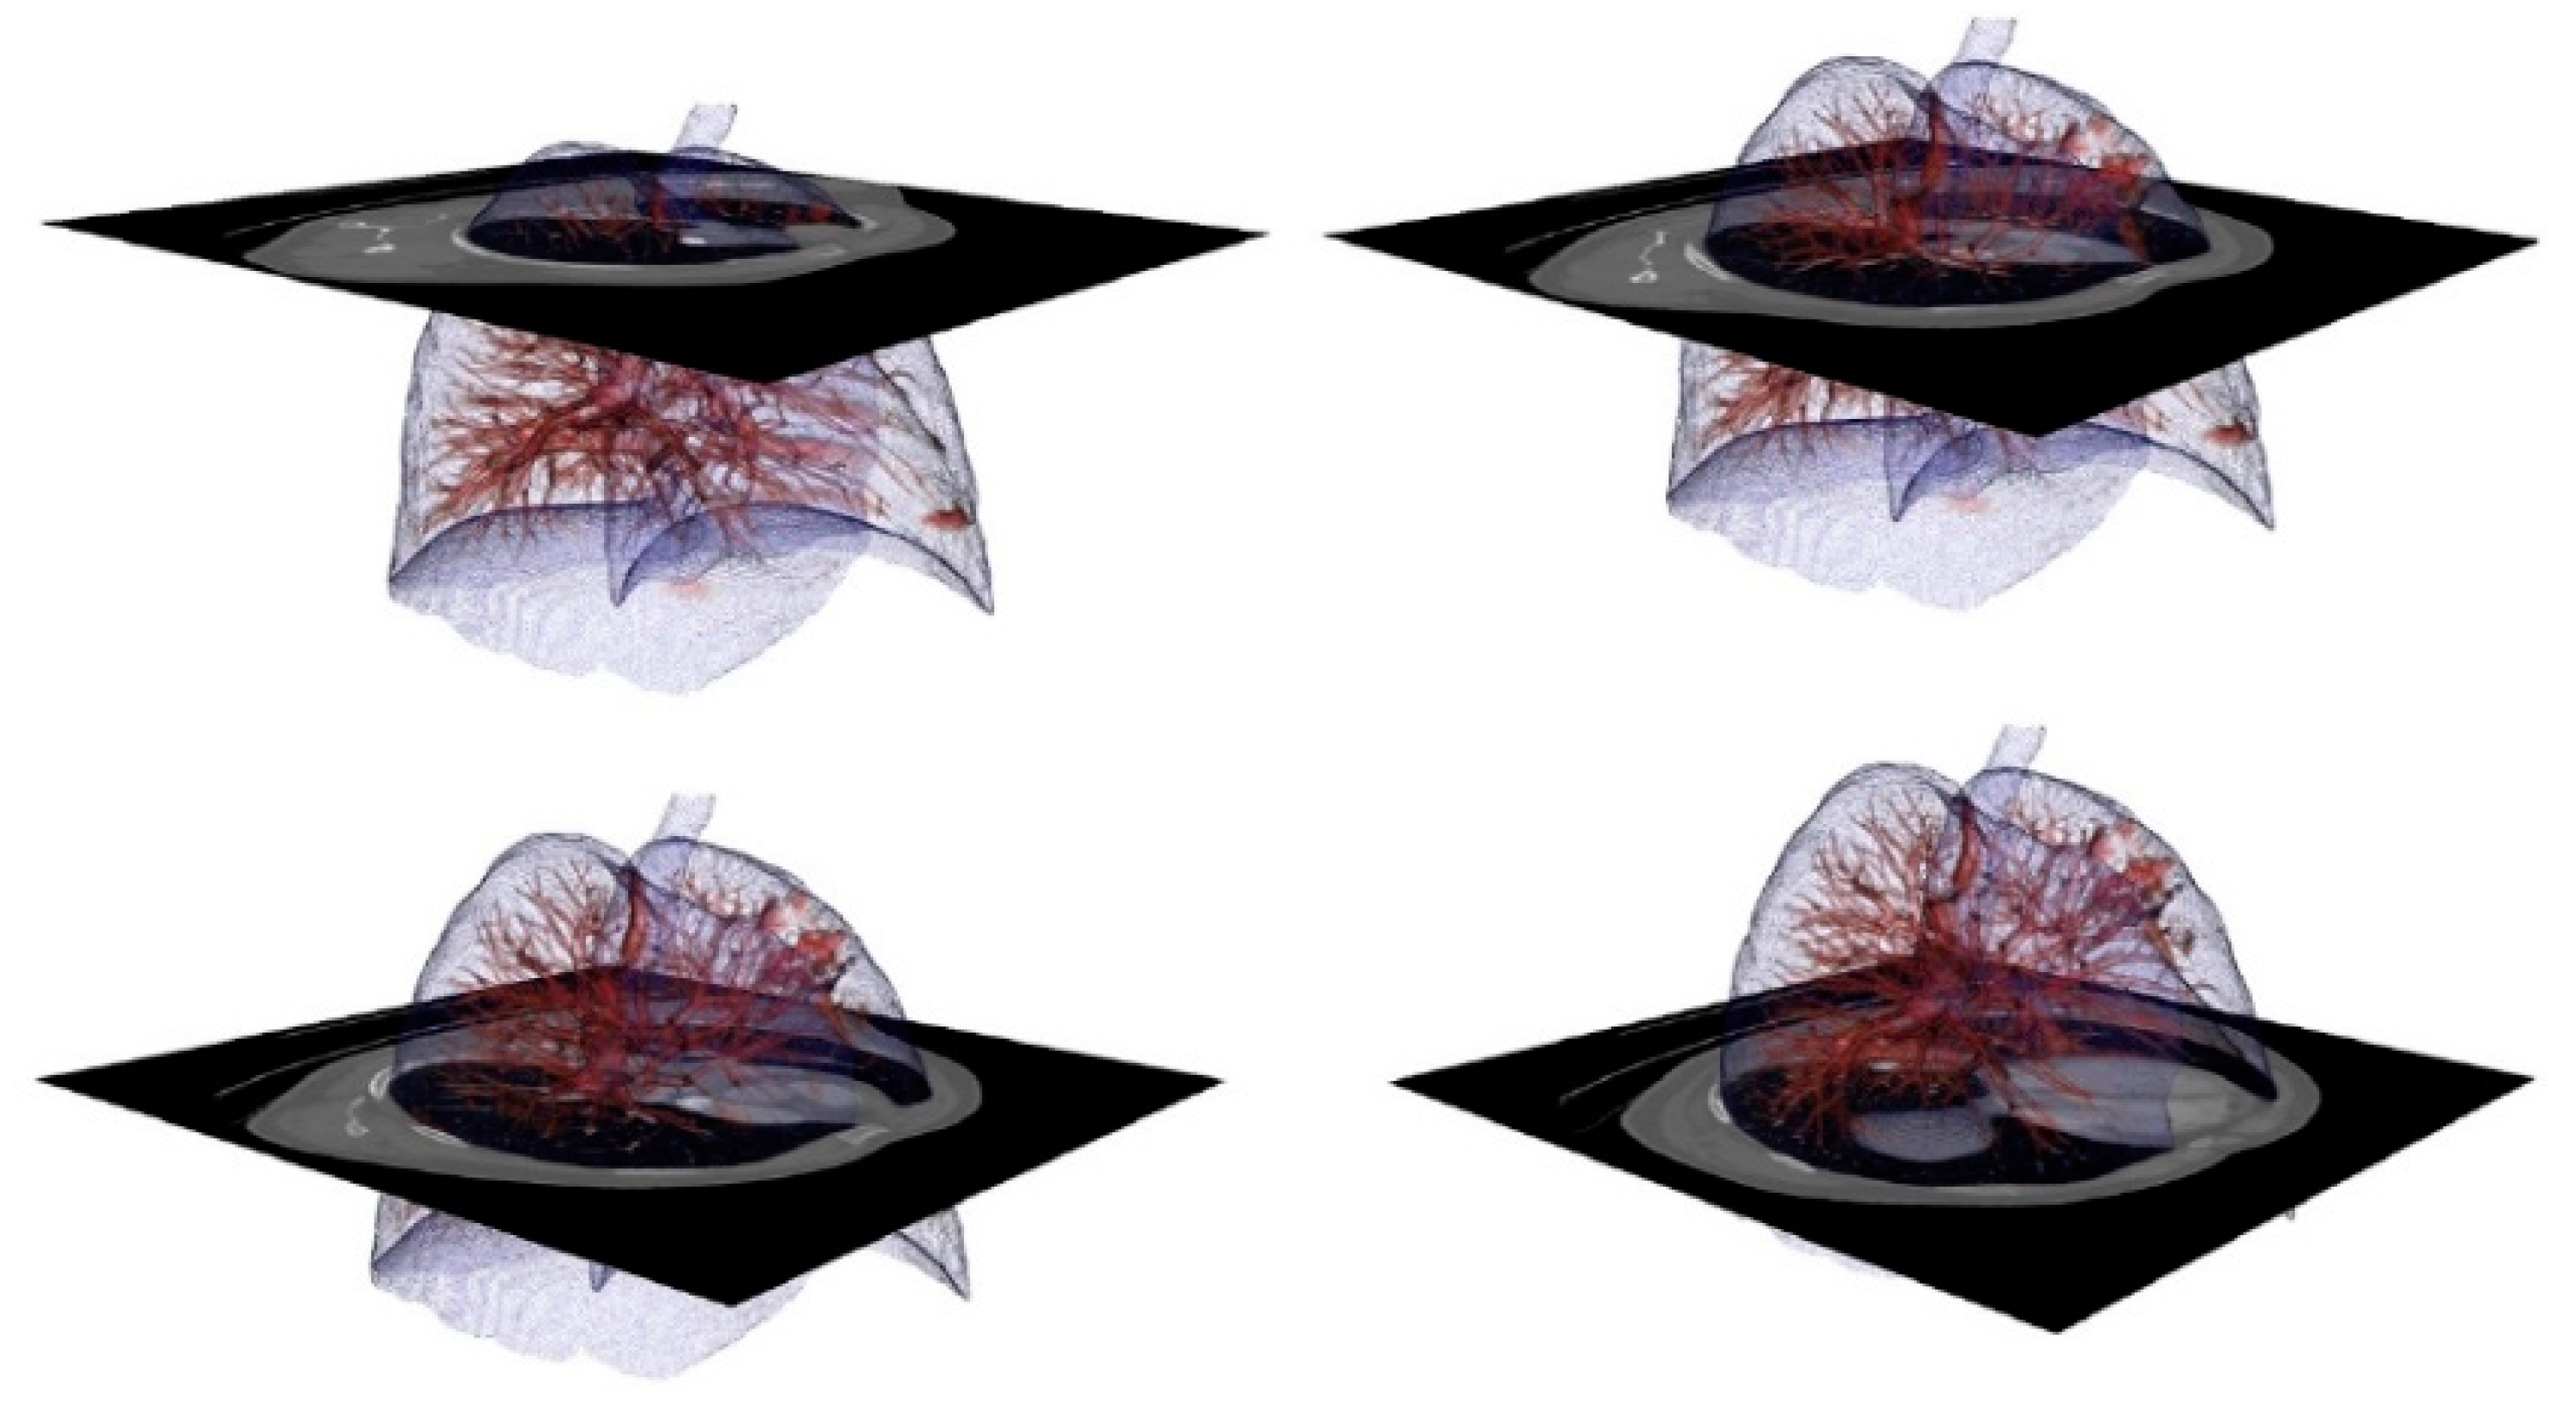

3.1. From dicom to 3D Models with Automatic Segmentation

3.2. Results Visualization